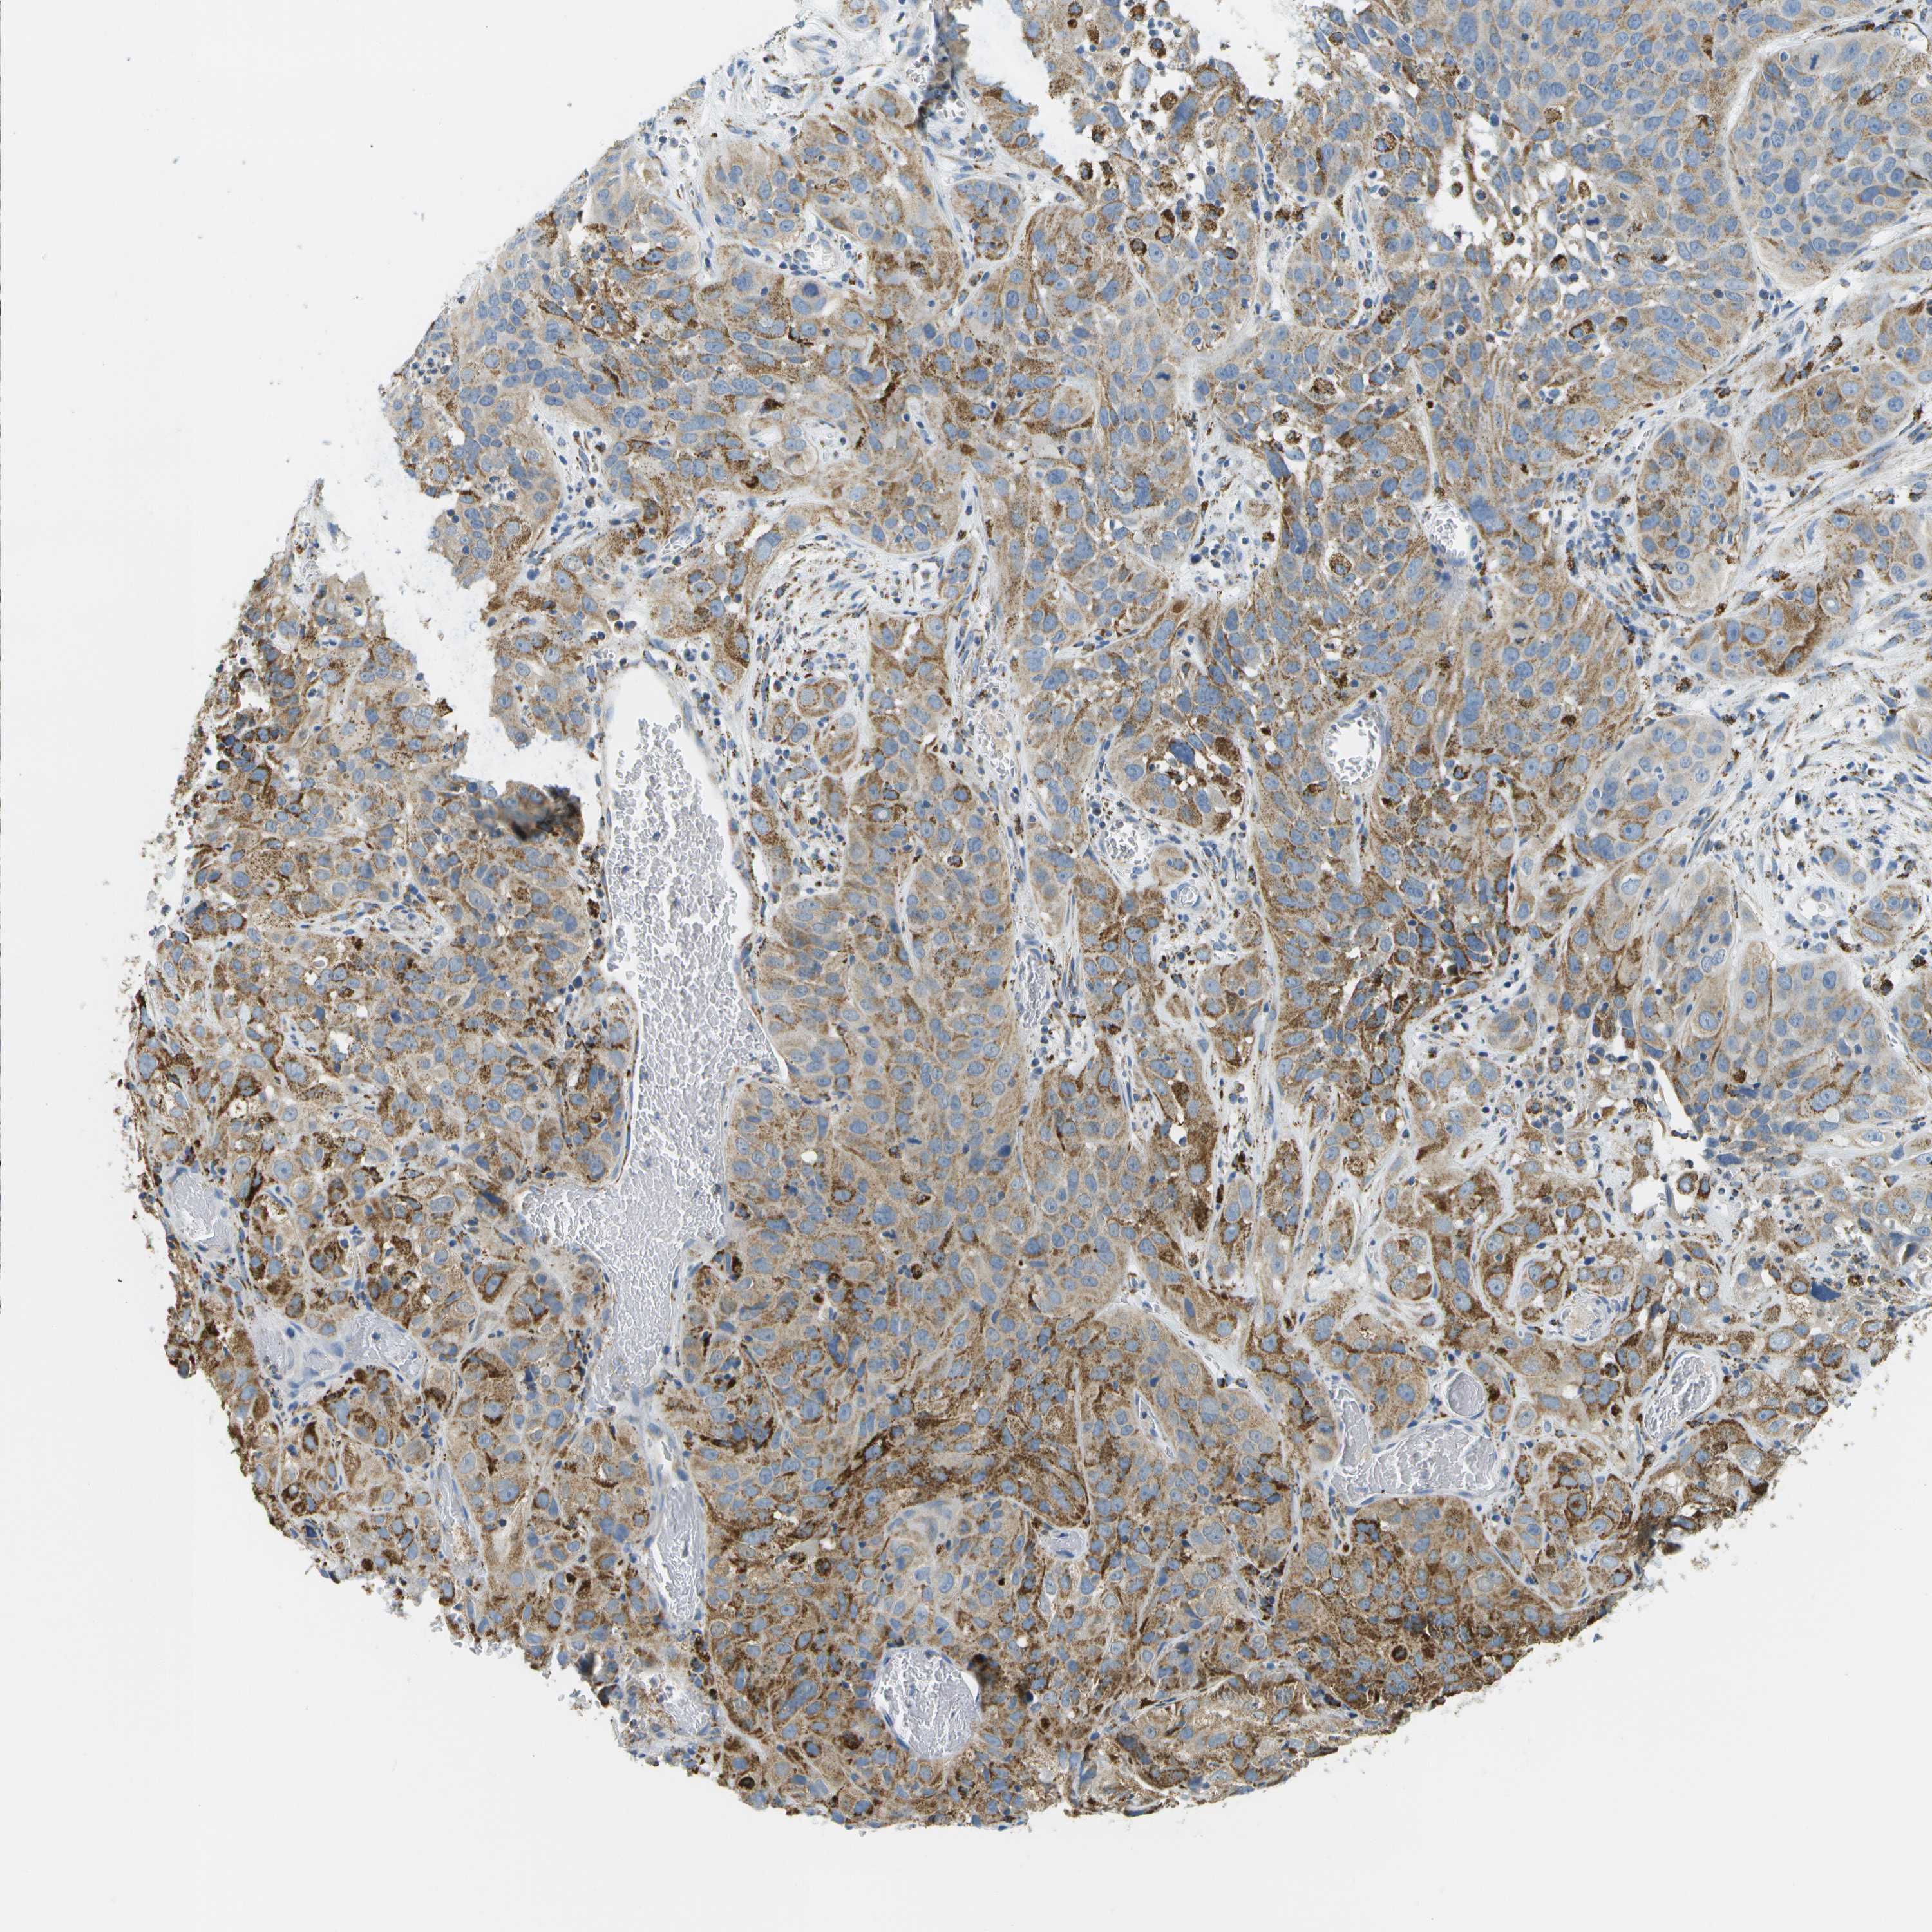

CERVICAL CANCER - Protein expressioni

A mouse-over function shows sample information and annotation data. Click on an image to view it in a full screen mode. Samples can be filtered based on level of antibody staining by selecting one or several of the following categories: high, medium, low and not detected. The assay and annotation is described here.

Note that samples used for immunohistochemistry by the Human Protein Atlas do not correspond to samples in the TCGA dataset.

Antibody stainingi

Antibody staining in the annotated cell types in the current human tissue is reported as not detected, low, medium, or high, based on conventional immunohistochemistry profiling in selected tissues. This score is based on the combination of the staining intensity and fraction of stained cells.

Each image is clickable and will lead to virtual microscopy that enables deeper exploration of all samples and also displays staining intensity scores, fraction scores and subcellular localization as well as patient and tissue information for each sample.

Antibody HPA017379

Staining

High

Medium

Low

Not detected

Intensity

Strong

Moderate

Weak

Negative

Quantity

>75%

75%-25%

<25%

None

Location

Nuclear

Cytoplasmic/membranous

Cytoplasmic/membranous,nuclear

Squamous cell carcinoma, NOS

Adenocarcinoma, NOS